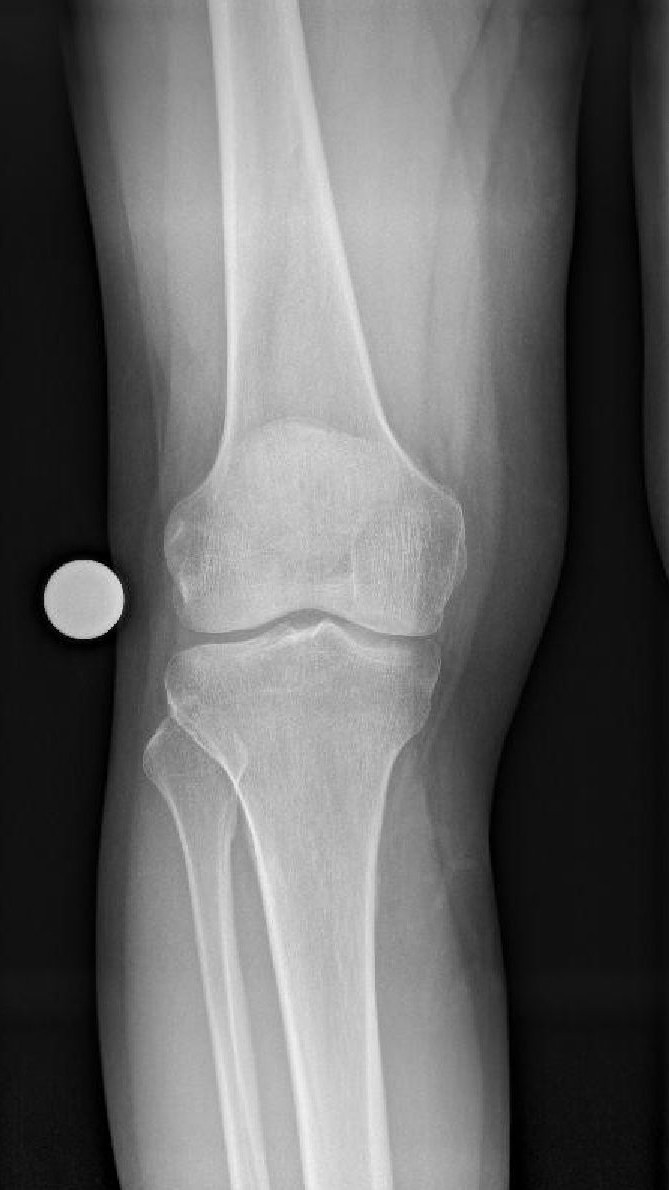

Die häufigste Fehlstellung des Knies ist das O-Bein, auch Genu varum genannt. Dabei kippen der Oberschenkel- und Unterschenkelknochen zur Außenseite des Beins, wodurch mehr Gewicht auf der Innenseite des betroffenen Gelenks ruht. Die Folge: die schützende Knorpelschicht nutzt sich auf der belasteten Seite übermäßig ab.

O-Bein vs. X-Bein

Liegt eine symptomatische Fehlstellung der Beinachse vor, wird diese mit speziellen Röntgentechniken objektiviert. Eine Kernspintomografie (MRT) zeigt darüber hinaus mögliche Begleitverletzungen. Anhand einer Ganzbeinaufnahme lässt sich die Fehlstellung präzise ermitteln und die Korrektur computergestützt planen.

O-Bein präoperativ